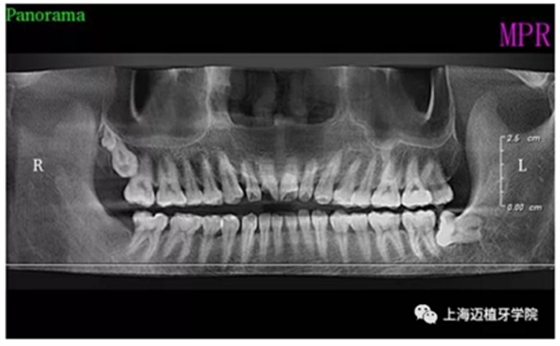

術(shù)前全景片

主訴:前門外傷牙根折要求修復(fù)?現(xiàn)病史:前門牙外傷,劈裂至根部,無法固定及其他修復(fù),要求種植?檢查:11牙冠2/3缺損,唇腭向劈裂,唇部紅腫。 CT示根折, 骨寬度9.47mm,距鼻底12.34mm,Ⅲ類骨。 口腔衛(wèi)生一般